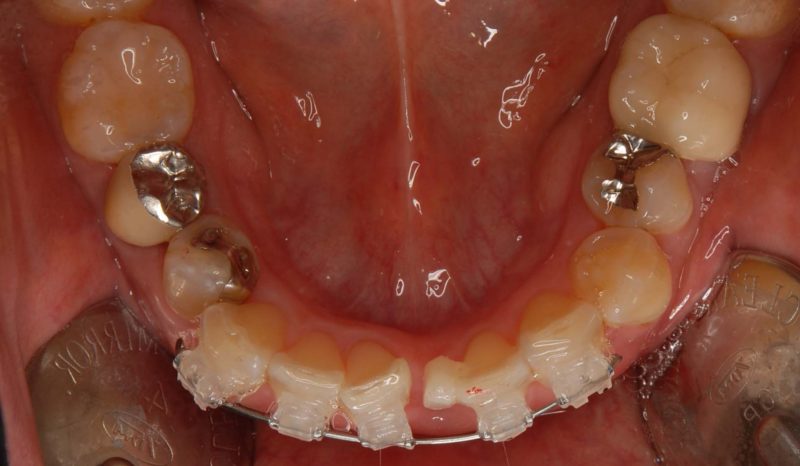

治療前: 前歯のみの治療を希望されました。

装置装着時: 前歯にのみブラケットをつけました。